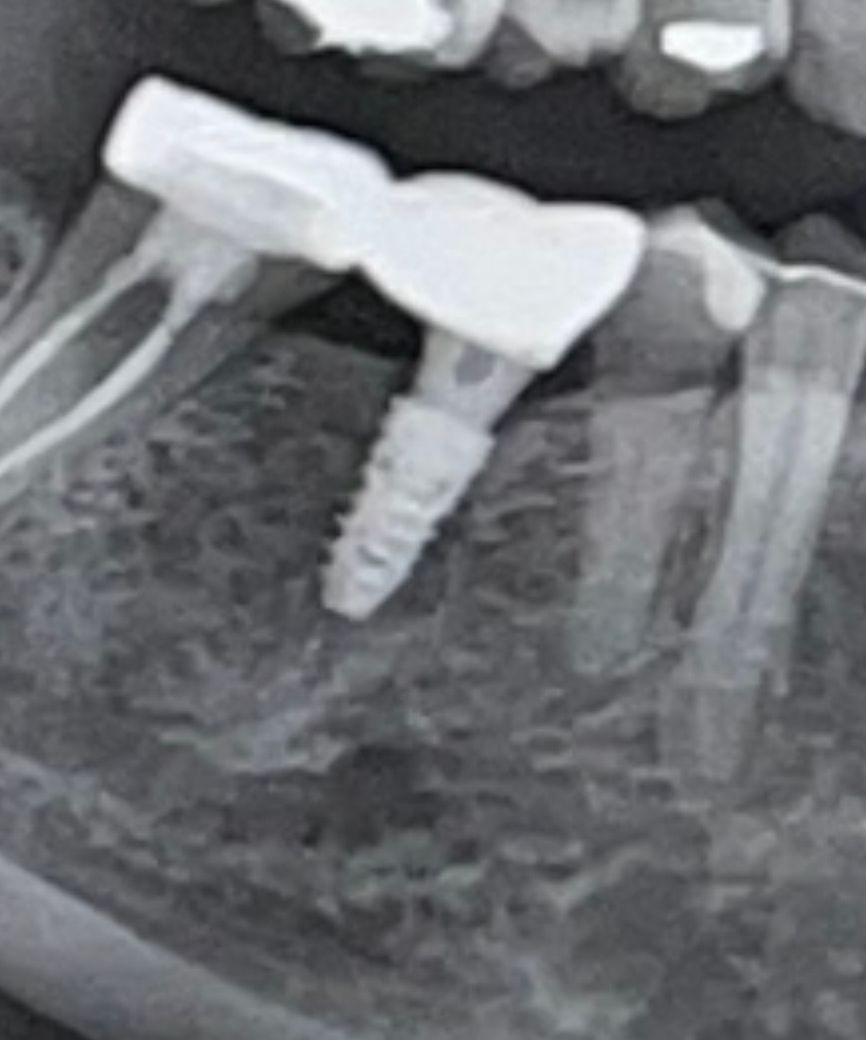

임플란트 치아에 염증이있는지 질문을 드렸는데 주변 잇몸뼈가 녹아있다는 답변을 받았습니다. 혹시 임플란트 재수술이 필요한 상태인건지 궁금합니다... ㅜㅜ 재수술이 아니라면 어떤 치료가 시급한가요?

사진상으로 임플란트가 크게 문제가 없어 보이니 잇몸치료를 받으면서 관리하시면될것같습니다.

임플란트 뿌리 주변에 뼈가 손실된 것으로 보입니다. 특별한 불편감이 없다면 임플란트에 너무 강하지 않은 힘을 작용해서 사용하는 방법이 있습니다. 불편감이 있다면 임플란트 뿌리가 탈락된 것일 수 있으니 재수술이 필요할 수도 있습니다

자세한 확인을 위해서 치과에서 진료를 받아보는 것을 권유드립니다.

x-ray 사진으로 볼 때 잇몸뼈 내려갔다는 증거 없습니다. 현재 불편한 것 없다면 그냥 두어도 됩니다. 만약 x-ray 에서 안보이는 것 때문에 통증이나 잇몸 붓는 것 있다면 치료해야 합니다.

보통 재수술은 마지막 수단입니다 그 전에 잇몸 염증 관련 처치 수술을 해보는 것을 권장합니다